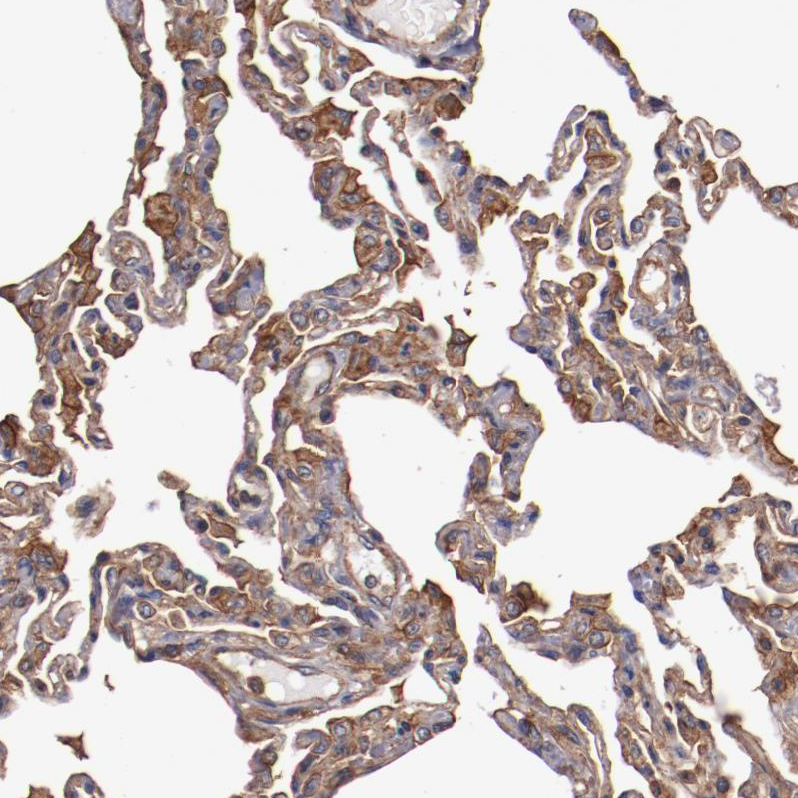

Immunohistochemical staining of human lung shows strong cytoplasmic positivity in pneumocytes.